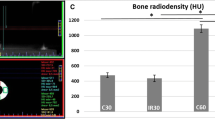

The means and standard deviations of all parameter analyses are shown on Table 1. In the macroscopy analysis, the IRnoHBO and IRHBO groups showed lower length values compared to noIRnoHBO and noIRHBO groups (p < 0.01). The thickness of the anteroposterior (AP) and medial-lateral (ML) parameters showed lower values in IRnoHBO and IRHBO compared to noIRnoHBO and noIRHBO groups, respectively (AP: p < 0.03 ML: p < 0.02). In addition, the IRnoHBO has no statistical difference in macroscopic analysis compared to IRHBO (p > 0.05).

The biomechanics analysis showed that the IRnoHBO group had lower value of flexural strength, when compared to the noIRnoHBO and IRHBO groups (p < 0.04). In addition, the noIRHBO group showed a higher value of flexural strength compared to noIRnoHBO and IRHBO groups (p < 0.02). The stiffness parameter showed that IRnoHBO had lower values compared to noIRnoHBO and IRHBO groups (p < 0.03), however, there is no statistical difference in noIRHBO, when compared to the IRHBO and noIRHBO groups (p > 0.06).

In the ATR-FTIR analysis, the IRnoHBO and IRHBO had lower values of collagen maturity, when compared to the noIRnoHBO and noIRHBO groups, respectively (p < 0.03). The crystallinity index showed that IRnoHBO and IRHBO had lower values, when compared to the noIRnoHBO and noIRHBO groups, respectively (p < 0.04). In addition, the organic/inorganic ratios (M:MI and M:MIII) showed that IRnoHBO and IRHBO had lower values compared to the noIRnoHBO and noIRHBO groups (M:MI: p < 0.01; M:MIII: p < 0.02).